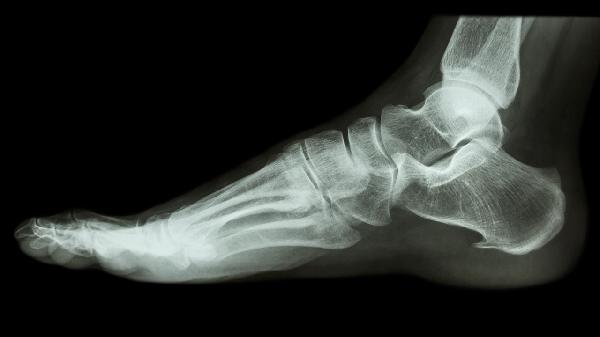

脚后跟骨折后可能出现足跟疼痛、创伤性关节炎、足弓塌陷、跟腱挛缩、慢性肿胀等后遗症。跟骨骨折属于严重损伤,多由高处坠落或交通事故导致,需通过影像学检查评估骨折类型后制定个性化康复方案。

骨折愈合后可能遗留持续性足跟疼痛,与跟骨关节面不平整或骨痂增生刺激周围软组织有关。疼痛常在负重行走时加重,可能伴随局部压痛。可通过穿戴矫形鞋垫减轻压力,严重时需考虑跟骨成形术修复关节面。

跟距关节面损伤后易发生退行性变,表现为关节僵硬和活动时摩擦感。早期可通过关节腔注射玻璃酸钠缓解症状,晚期关节严重破坏时需行关节融合术。康复期间应避免跳跃等冲击性运动。

跟骨高度丢失会导致足弓支撑力下降,引发扁平足畸形。患者可能出现步行易疲劳、足底筋膜炎等症状。定制足弓支撑器配合小腿三头肌力量训练可改善症状,严重畸形需行截骨矫形手术。

骨折愈合后应定期复查跟骨CT评估复位情况,康复期坚持踝泵运动和本体感觉训练。控制体重减轻足部负荷,选择硬底鞋提供足够支撑。出现进行性加重的疼痛或畸形应及时就诊,避免后遗症进一步加重影响行走功能。饮食注意补充钙质和维生素D促进骨愈合,每日进行30分钟水中步行训练可减少关节负担。